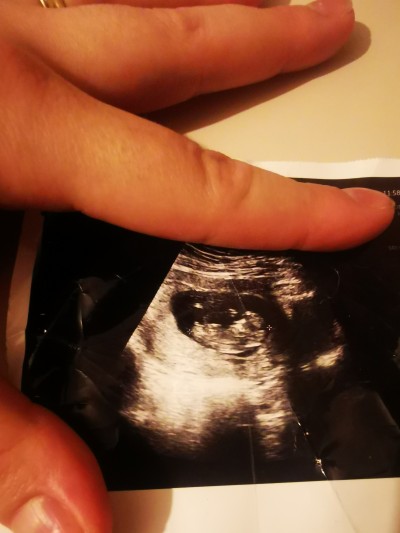

Kızlar burası tam olarak bebişin neresi bacaklarının arasında bi çıkıntı var erkekmi acaba

Kordona benziyo  yandan  görüntü 11... 12 haftalık gibi duruyo sani   görünmüyo canım cinsiyet i

11 12 haftalık evet bende merak ettm sadece

Bacak arası gibi kız sanki Dr ne dedi

Valla dr da kız olabilir dedi

12 haftada cinsel organları yeni oluşuyor çıkıntı kordondur. Hislerim kız diyor hayırlı evlat olsun

Cnm bebeğin baştan popoya kadar ölçümünü yapmışlar sol yani görünüyor bebeğin bu şekilde cinsiyeti bilmek imkansız malesef  bacak arası görünmüyor çünkü